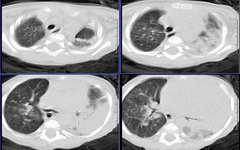

患儿 六月 咳嗽,反复发热二周,加重伴气喘3天

左肺呈大片状实变影,密度欠均匀,边界模糊,残存正常的肺组织呈气肿表现,右肺内可见磨玻璃样改变,如此年幼的婴儿首先考虑左肺发育不良并继发感染可能性大

此患儿于前日死亡,病检结果:

左肺发育不良伴感染.